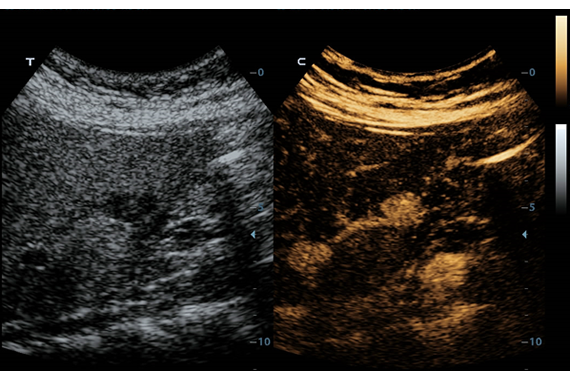

Система ультразвукового исследования Mindray DC-60 EXP X-INSIGHT является новейшей разработкой для проведения комплексных обследований на высшем уровне. Она обеспечивает решение самых сложных задач в таких областях, как кардиология, акушерство и гинекология, сосудистые заболевания, педиатрия и многие другие.

DC-60 EXP X-INSIGHT - это современный стационарный УЗИ-аппарат с функцией сенсорного управления и очищенной гармонической визуализацией, обеспечивающей лучшее контрастное разрешение и технологию 4D-визуализации. Он оснащен 21,5-дюймовым монитором, который может поворачиваться на 180 градусов, что удовлетворяет потребности врачей в качественной ультразвуковой диагностике.

Одним из ключевых преимуществ DC-60 EXP X-INSIGHT является технология формирования УЗ-луча. Она дополняет основной луч параллельно эхо-сигналами, что приводит к получению более мощного сигнала и изображений высокого качества с помощью систем iLive, iPage, Smart OB, Smart NT.